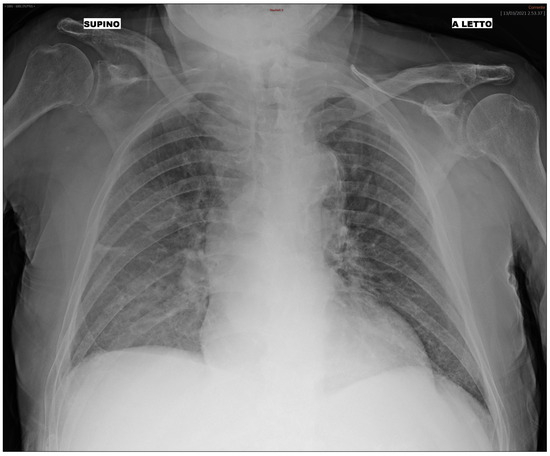

We additionally analyzed the BN and RF performance and their misclassification errors in light of prognostic outcomes that were collected after the initial diagnosis for each patient of the third wave set. In summary, each patient included in the study (both treated at home or in hospital), underwent follow-up, and clinicians recorded the outcomes after some time from the initial diagnosis. Patients with mild outcomes were those not hospitalized or hospitalized without the need for ventilation support. Patients with moderate outcomes were hospitalized with airway pressure device support, while severe patients were those hospitalized with invasive ventilatory support or who were deceased. We analyzed misclassification errors by the BN, and we correlated it with the follow-up outcome. We found that, for False Positive patients (i.e., patients predicted “hospital” where in fact they were treated at home at the beginning), a higher percentage of severe and moderate patients were detected. In False Negative patients, most of them had a mild outcome. For instance, we present the case of a 92-year-old male patient who underwent triage during the third wave. The patient did not present with cough, dyspnea, or any significant functional impairment. The CXR image of the patient is depicted in Figure 3 and shows alteration mainly in the right lung. Both the BN and the RF incorrectly predicted the “Hospital” class, while the patient was not initially hospitalized. However, 7 days after the first triage, the patient returned to the ER with worsened symptoms and was subsequently hospitalized. This serves as an example of where the ML prediction contradicts the ground truth (i.e., the medical decision during the first triage). Nonetheless, the progression of the disease, leading to a delayed hospitalization, implies that the ML prediction might have been correct, suggesting an alternative scenario to clinicians at the time of the initial triage of the patient. The availability of the prediction from the algorithm during the first triage might suggest more caution to the clinician in weighing the chest X-ray with other factors (such as the age of the patient) and leading to more safe management even when a functional impairment is not yet present.

Figure 3. Bedside CXR image of a 92-year-old patient classified by the ML as “Hospital”.